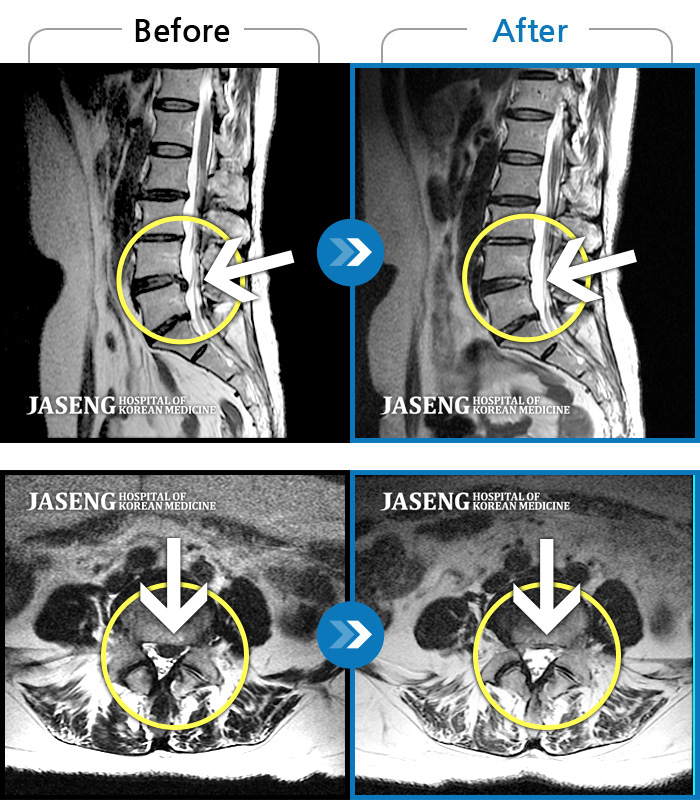

허리디스크

안산 · 김민수 원장

발목의 힘이 떨어져서 절뚝거리면서 걸었다.

촬영시기

2022.01.03 ~ 2024.07.31

2024.08.09

조회수 518